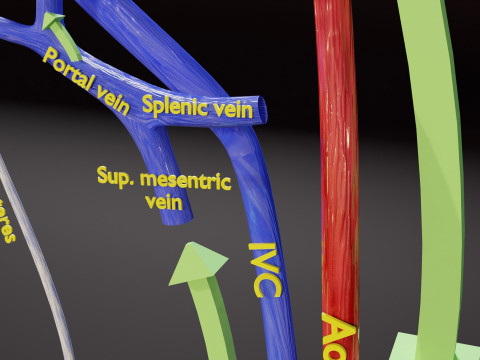

The model meshes include adult circulation versus circulation in Tetralogy of Fallot (TAF), arrow labels and text labels. The blood flow in a patient with Tetralogy of Fallot is outlined in this model. To contrast it to normal blood circulation a separate model of normal circulation is included. The Tetralogy of Fallot (OVER RIDING OF AORTA, PUL STENOSIS, VENTRICULAR SEPTAL DEFECT, RIGHT VENTRICULAR HYPERTROPHY), fossa, ligament teres , venosus, and arteriosus are duly depicted with proper labelling and blood flow directional arrows. Excellent model for teaching, demonstration and knowlegde of human body. The models include both procedural and image textures blend files separately. The texture file include diffuse, roughness and normal png and jpeg based on non overlapping UV maps.